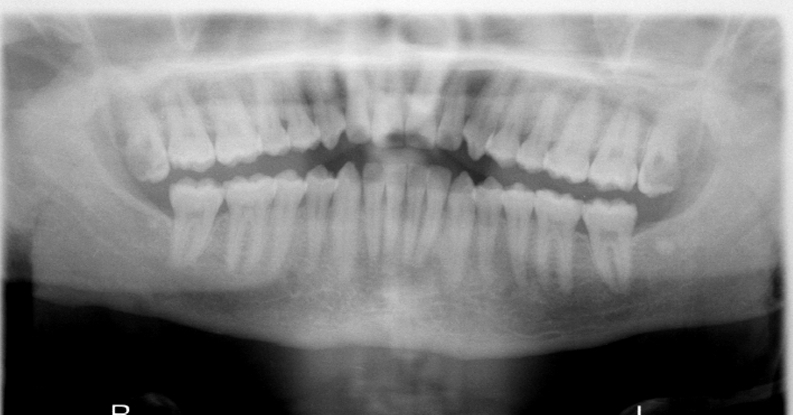

32

What is wrong with this image?

TONGUE NOT AT ROOF OF MOUTH - palatoglossal air space